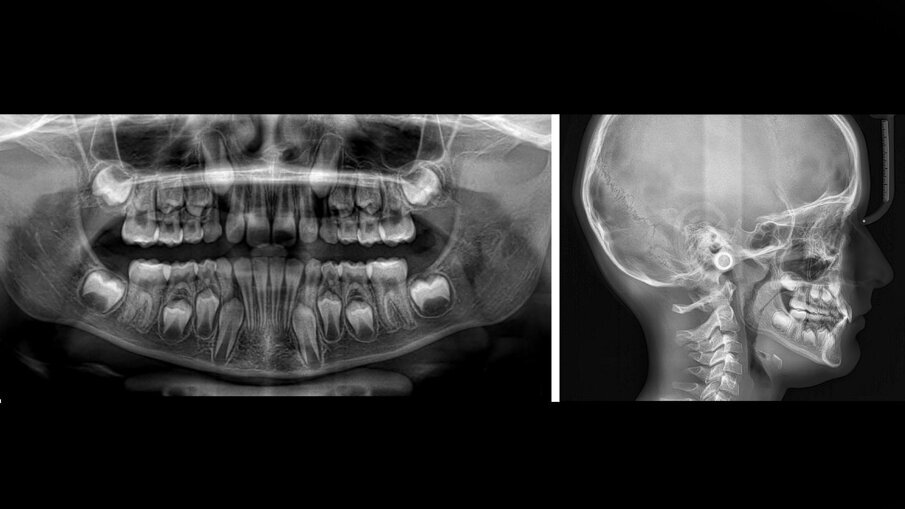

L’ortopantomografia mostrava uno stadio E secondo la classificazione di Demijrian4, affollamento zona apicale nella zona intermedia e anteriore, mentre la teleradiografia laterale confermava la malocclusione di prima classe scheletrica mesodivergente (Figg. 2a-2b). Senza segni né sintomi di problemi basali né respiratori, a circa 24 mesi dal picco puberale, il paziente presentava la necessità di recupero di spazio per lo sviluppo dell’occlusione armonico delle arcate dentarie. La terapia ortodontica precoce con allineatori Nuvola Genius è durata complessivamente 11 mesi ed è consistita in due fasi. La prima di 24 allineatori superiori e inferiori (Fig. 3) e la seconda di rifinitura di 14 allineatori superiori e 12 inferiori.

Fig. 2a-2b_Records radiografici pretrattamento.